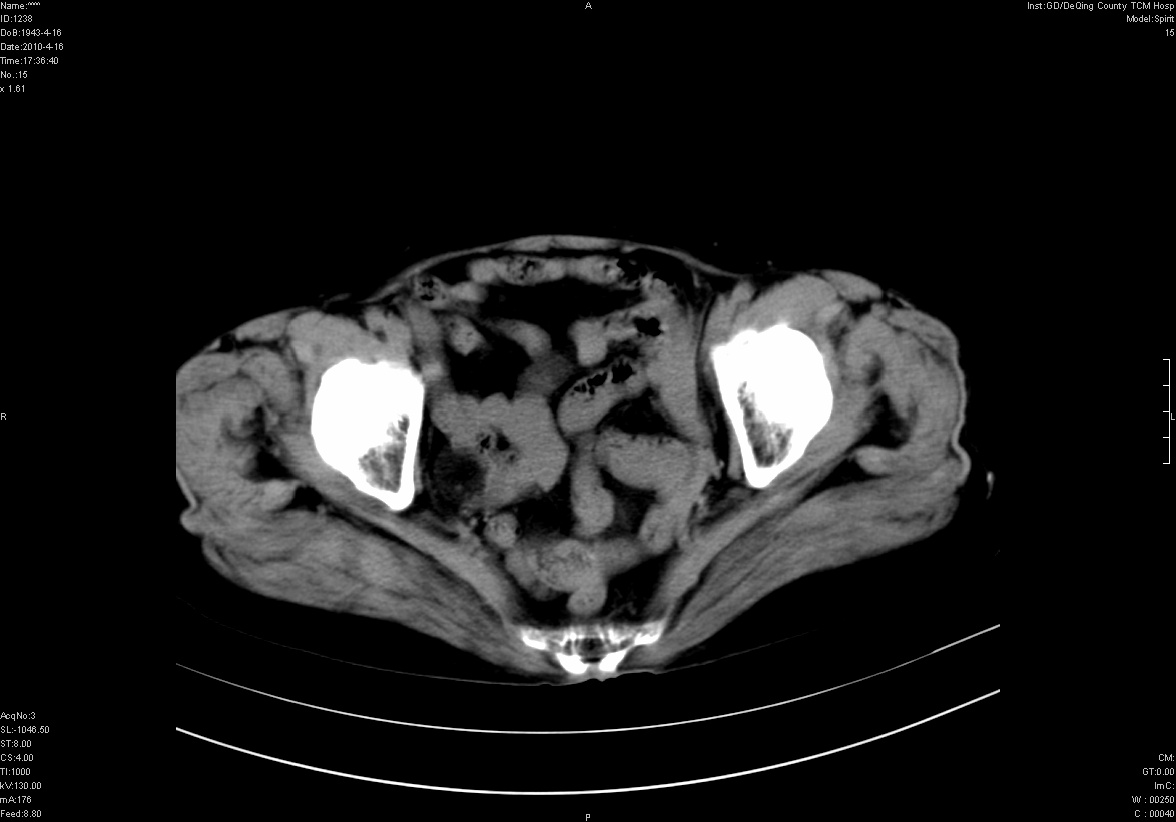

标题: CT25796:女,60岁,腹痛5天,请会诊??? [打印本页]

标题: CT25796:女,60岁,腹痛5天,请会诊???

是要我考虑粪石吗?引起阑尾炎

考虑卵巢畸胎瘤。

支持右侧盆腔畸胎瘤。

畸胎瘤

右侧附件畸胎瘤

不太像畸胎瘤,粪石。

考虑右侧卵巢畸胎瘤。

考虑右侧卵巢畸胎瘤

右侧卵巢畸胎瘤可能。